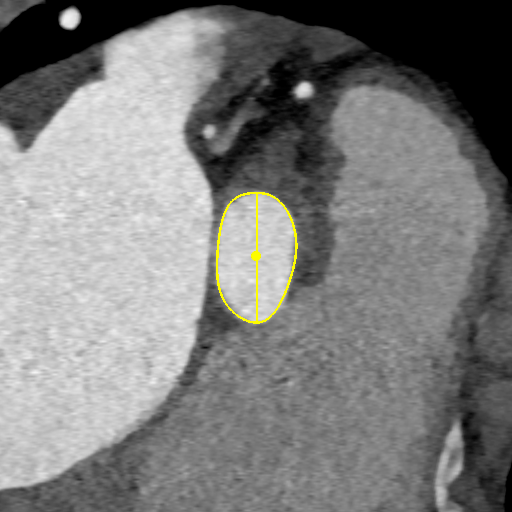

CT测量

主动脉根部CT

瓣环平均直径:

22mm

左室流出道平均直径:

23.3mm

窦宽:32/30/31mm

横位心:48°

左冠开口高度:

13.5mm

右冠开口高度:

10mm